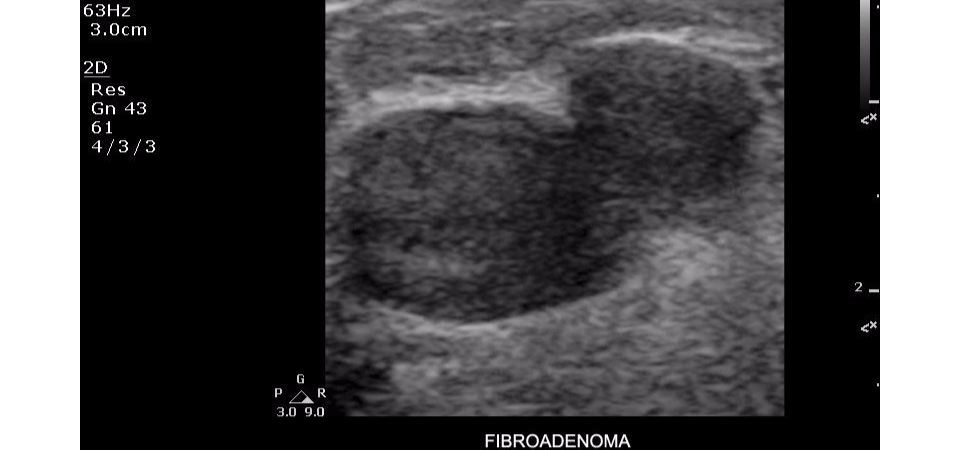

Philips ClearVue 350 представляет собой современную ультразвуковую систему, которая сочетает в себе передовые технологии визуализации, удобство использования и широкие диагностические возможности. Благодаря инновационным решениям и продуманной эргономике, система обеспечивает высокую эффективность работы медицинского персонала.

Технология XRES: Фирменная технология обработки изображений Philips в сочетании с предустановленными настройками датчиков значительно повышает качество визуализации и достоверность диагностики.

• Широкополосное формирование ультразвукового луча с усовершенствованной обработкой сигнала для точной дифференциации тканей

• Режим тканевой гармоники для подавления артефактов при сохранении высокого разрешения

• Абдоминальные исследования

• Урология